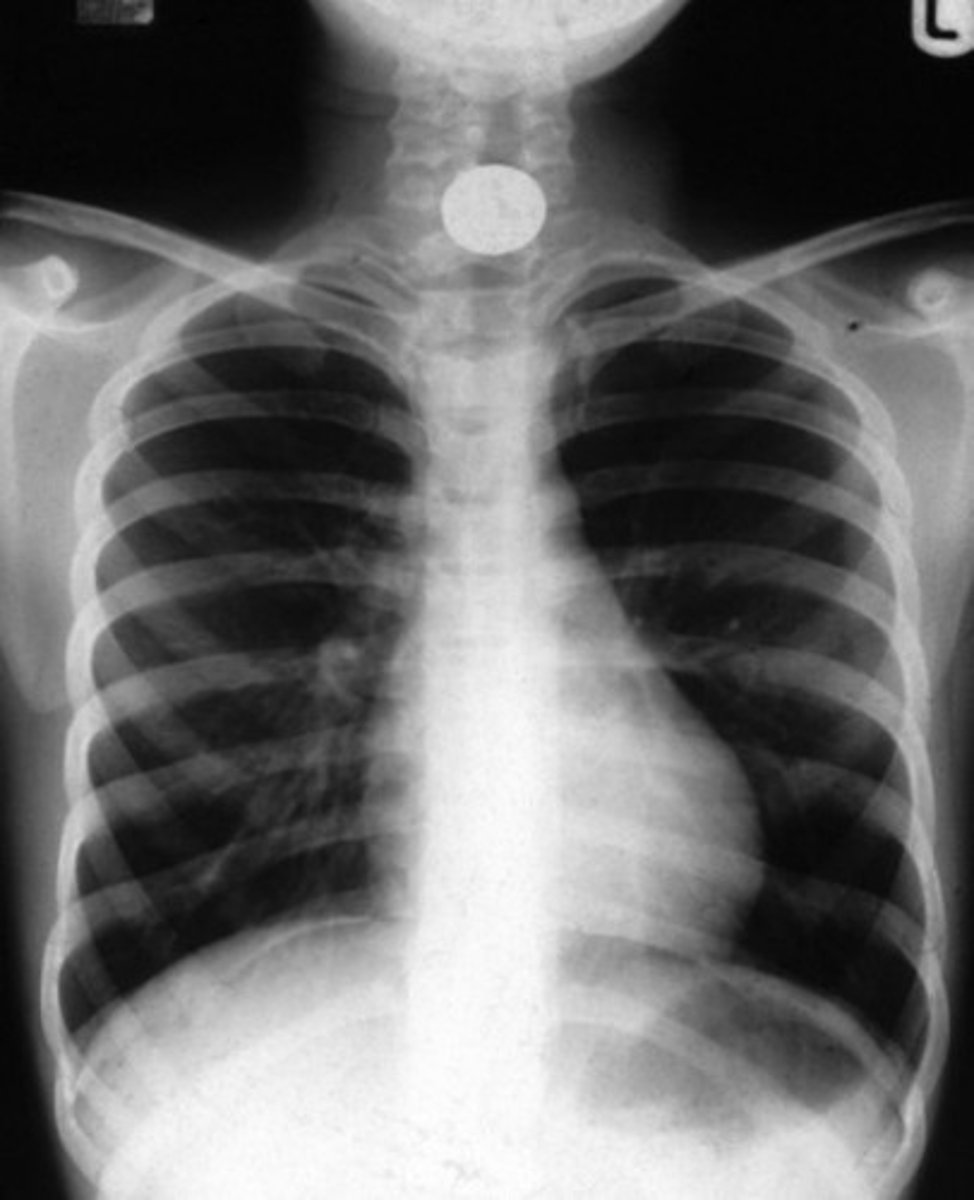

Which imaging modality is usually the first line investigation for foreign bodies?

- usually plain film x-rays.

What are the advantages of using plain x-rays for foreign body imaging? List them.

• Readily available

• Image manipulation /windowing can be used to enhance the potential visualisation of a FB

• Radiopaque markers can be safely placed on the cassette / detector to identify the position of any entry-wounds

• Useful for pre-MRI orbital survey projections

• Fluoroscopy can be used in theatre to assist in the removal of radiopaque FBs

What are some disadvantages of using plain x-rays for foreign body imaging?

• Limited ability to detect certain materials e.g. wood, plastic and some types of glass

• Limited ability to detect certain types of fish bones which are radiolucent.